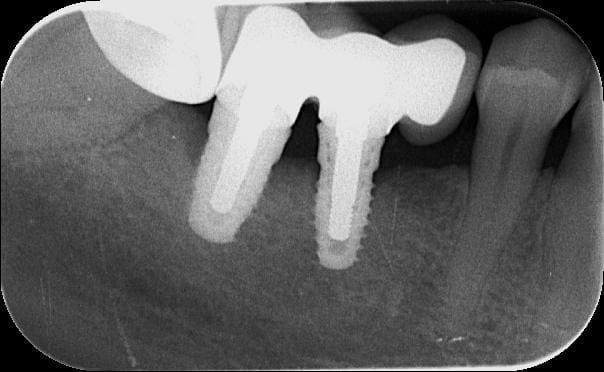

j'ai posé deux easy avec le biseau enfoui dans l'os. A 3 mois, pose des piliers de cicatrisation et un mois plus tard pose de la prothèse.

manifestement l'os ne reste pas en place à ce niveau

je prendrai un cliché dans 3 mois pour évaluer ce qu'il advient de la zone mésiale du col de l'implant distal.

46 47 xvjblf - Eugenol

46 47 pose kiaay7 - Eugenol